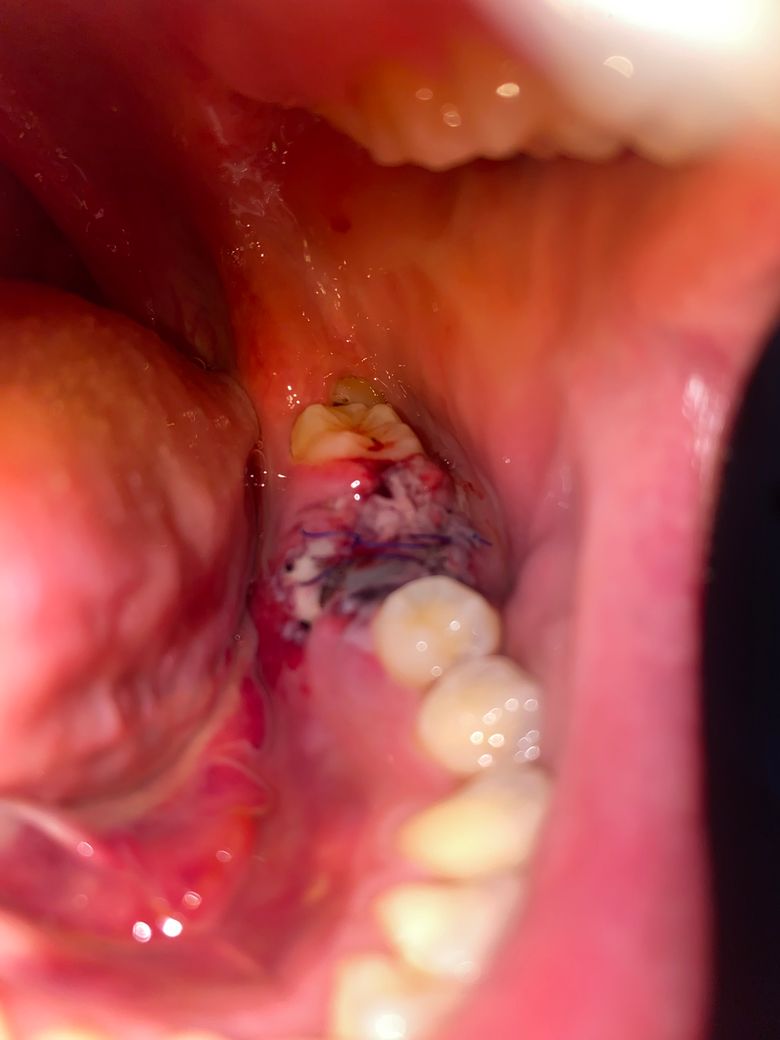

어금니 발치 4일차인데 이거 정상인가요?

염증이 잇몸뼈를 다 녹여 어금니 발치후 상당량 뼈이식을 한 상태입니다. 4일차인데 실도 느슨해보이는게 풀린지 궁금하고, 원래 아무는 과정에서 저렇게 검고 하얀 얼룩같은게 지저분하게 보이는게 정상인건가요?

잇몸이 치유되는 과정중에 생기는 자연스러운 현상입니다. 최대한 자극이 가지 않도록 해줘야 잇몸이 잘 아물꺼에요.

특별히 문제가 보이지는 않습니다. 붓기가 있기 때문에 실밥이 느슨해질 수 있으며 문제는 없어보입니다.

현재 정상적인 치유 반응으로 보입니다. 하지만 통증, 부기, 고름이 나오면 염증이나 감염을 의심할 수 있습니다. 해당부위에 염증이 덧나지 않도록 소독용 헥사메딘 가글액으로 가글하여 관리하여 주고, 통증이 심하거나 부기가 지속되는 경우, 혹은 고름이나 악취가 나는 경우에는 즉시 치과 진료를 받길 권합니다.

만족스러운 답변되셨으면 합니다.